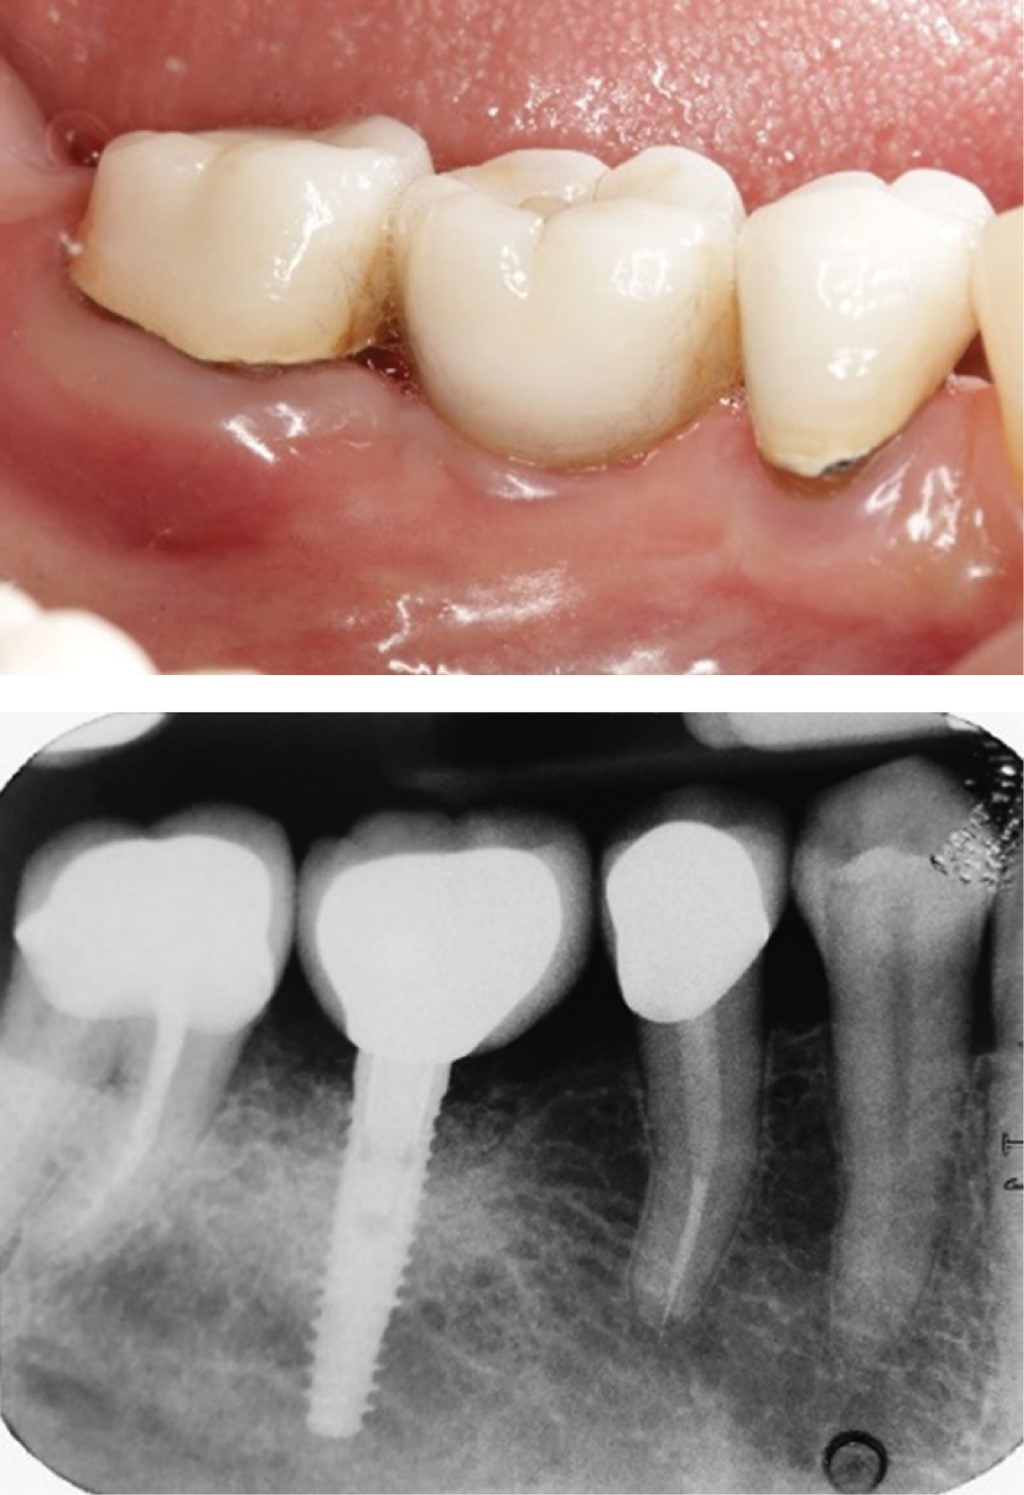

Para el abordaje quirúrgico reconstructivo y bajo previa infiltración local de anestesia, se levantaron colgajos a espesor total para exponer el cuerpo del implante, se eliminó el tejido de granulación con la ayuda de curetas de titanio y se procedió a la descontaminación de la superficie del implante mediante el uso de un cepillo rotatorio de cerdas de nylon, se irrigó implante con peróxido de hidrógeno al 3% y finalmente con cloruro de sodio al 0.9%. Finalmente, se rellenó el defecto óseo con hueso anorgánico mineral bovino en gránulos pequeños (Bio-Oss, Geistlich Pharma, Suiza), no se colocó ninguna membrana sobre el sustituto óseo, se reposicionaron los colgajos y se suturaron con nylon 5-0 (Figura 2).

Se indicaron como medias postoperatorias evitar el cepillado de la zona intervenida durante 15 días y mantener la higiene de dicha zona con la ayuda de un gel de clorhexidina al 0.20%. Además, se indicó un esquema de amoxicilina de 500 mg vía oral cada ocho horas por cinco días e ibuprofeno de 400 mg cada seis horas por tres días y se realizó el retiro de los puntos de sutura a los 15 días.